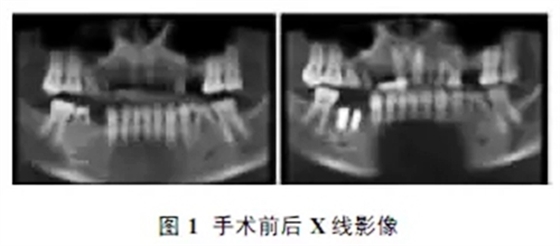

患者男性,33歲,右下后牙部分缺失1年。4個(gè)月前于我院行右下第一磨牙殘根拔除術(shù)及45、46種植體植入術(shù),分別植入Ankylos系統(tǒng)3.5mm×9.5mm及4.5mm×9.5mm種植體兩枚(如圖1)。

45植入過程中,中央螺栓平齊種植體平臺(tái)處斷裂。檢查:種植區(qū)牙齦無紅腫,種植體無外露,CBCT示種植體與骨接觸良好,種植體周圍無明顯骨吸收;45種植體中央螺桿處見線形折斷影(如圖2)。